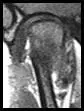

Joint analysis includes MRI and CT scans to be cross-referenced to gain a three-dimensional picture of the bone structures and the condition of the soft tissues.

The cartilage disk may be stuck or "adheased" to the bone or slipped forward or to one side or distended and degraded. All of the soft tissue in the joint capsule is evaluated.